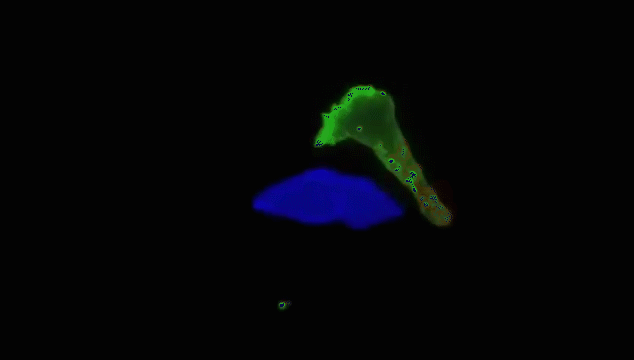

人体细胞总数在40~60万亿个之间,在这么多的细胞里,一些正常细胞由于物理、化学、病毒等致癌因子导致的原癌基因和抑癌基因突变后,就变成了癌细胞。一个正常人,每天会因各种原因产生6000个左右的癌细胞,而人体的免疫细胞则负责消灭癌细胞。美国细胞生物学会(ASCB)发布了一则微观大片,使用顶级的成像工具和技术,从免疫角度展示了人体中的一种免疫细胞T细胞杀死癌细胞的全过程。每个T细胞大约是人类头发直径的十分之一,它们在人体内不断巡逻,找出并杀死癌细胞或感染了危险病毒的细胞。当T细胞发现癌细胞时,通过分泌的毒素附着在癌细胞上,来检测、分辨正常细胞与癌细胞。查明之后,T细胞连接癌细胞,打破癌细胞外壁,向其表面引入毒性蛋白。一旦细胞毒素进入,癌细胞会逐渐衰弱、死亡。而T细胞继续在人体内巡逻,寻找下一个目标。其实除了上面提到的T细胞以外,身体里面还有很多免疫细胞在保护着我们,它们与癌细胞斗智斗勇,以抵御病毒保卫身体为终极目标。给大家分享几张免疫细胞“杀敌”的动图,来看看帅气的它们是如何英勇作战的:吞噬细胞在固有免疫中发挥重要作用,是清除致病微生物的重要免疫细胞。吞噬细胞包括两大类,即中性粒细胞(小吞噬细胞)及单核/巨噬细胞(大吞噬细胞)。两类吞噬细胞对入侵体内的微生物可极为快速的产生应答,尤以巨噬细胞的作用更为持久,是参与晚期固有免疫应答的主要效应细胞。NK细胞是T和B细胞并列的第三类淋巴细胞,不同于T、B细胞,它是具有直接杀伤靶细胞效应的一类淋巴细胞,靶细胞包括肿瘤细胞、病毒或细菌感染的细胞及机体某些正常细胞。NK细胞率先吹响战斗号角,以癌细胞头部为突破口发起进攻,癌细胞负隅顽抗NK细胞头部部队成功突破,大部队快速抵达战场,癌细胞瞬间瓦解NK细胞具有抗肿瘤、抗感染、免疫调节等功能,在病毒和寄生虫的抗感染免疫早期发挥重要作用。B细胞是体内产生抗体(免疫球蛋白)的细胞,B细胞也存在不同的亚群,主要执行体液免疫,也具有抗原提呈功能。通常情况下,人体的免疫系统可以高效地识别和消灭癌细胞,保证我们的身体健康。这些人体的天然“健康卫士”,绝对不会放过每一个逃逸的癌细胞。即便癌细胞成功逃逸进入血液,免疫细胞也会对癌细胞发起猛烈进攻。免疫细胞可穿过血管壁奔赴“战场”,向炎症和创伤组织进军、围剿。随着人类生命科学的不断发展,科学家们揭示了免疫细胞杀死癌细胞的作用机制,并证实了免疫细胞在对抗癌症上具有无可比拟的先天优势,根据这一特性,人类科学家探索出一系列通过补充T细胞、NK细胞、甚至使用CAR-T、CAR-NK等“大杀器”,来对抗癌症的免疫疗法。厉害了!我的免疫细胞!与病菌抗争的场面简直可以拍成一部精彩的战争电影了!想象一下,如果身体缺少它们每天顽强地抗敌的话,我们会怎样呢?应该连最基本的呼吸都难以做到了吧,毕竟空气中有那么多细菌,少了免疫细胞我们真没办法存活了......但是还是想跟大家说的一个真相是,免疫细胞虽然很强大,但是它们也会随着身体的老化而变得衰弱甚至死亡。因为少了免疫细胞的保护,身体对外来病毒的抵抗力就会变弱,人就会很容易生病。 |